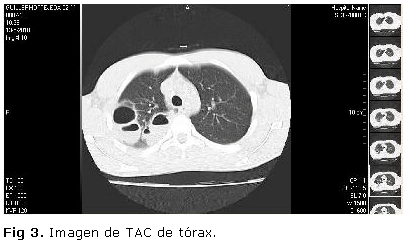

Imágenes radiopacas con niveles hidroaéreos en su interior y áreas radiopacas difusas alrededor de las mismas en relación con abscesos pulmonares en evolución con signos de neumonitis asociada. En la vista lateral, se comprueba que dichas lesiones se encuentran localizadas en el segmento posterior del LSD. TAC de Tórax (Figura 3).

Se realizó Tomografía axial computarizada (TAC) de Tórax simple en equipo Shimadzu Monocorte con cortes a 7 mm y reconstrucciones en MPR (siglas en inglés de multiplanar reformation) donde se comprueba la existencia de varios abscesos pulmonares con niveles hidroaéreos localizados en el segmento posterior del LSD derecho, de los cuales los mayores se encuentran 2 hacia la parte más lateral del mismo, que miden 4,9 cm. en corte axial, 4,6 cm. en corte coronal y 6,1 cm. en corte sagital y 3 cm. en corte axial, 3,2 cm. en corte coronal y 4,3 cm. en corte sagital, respectivamente, y uno hacia la parte más medial del mismo que mide 4 cm. en corte axial, 3 cm. en corte coronal y 3,8 cm. en corte sagital. Estos abscesos se acompañan de signos de neumonitis perilesionales.